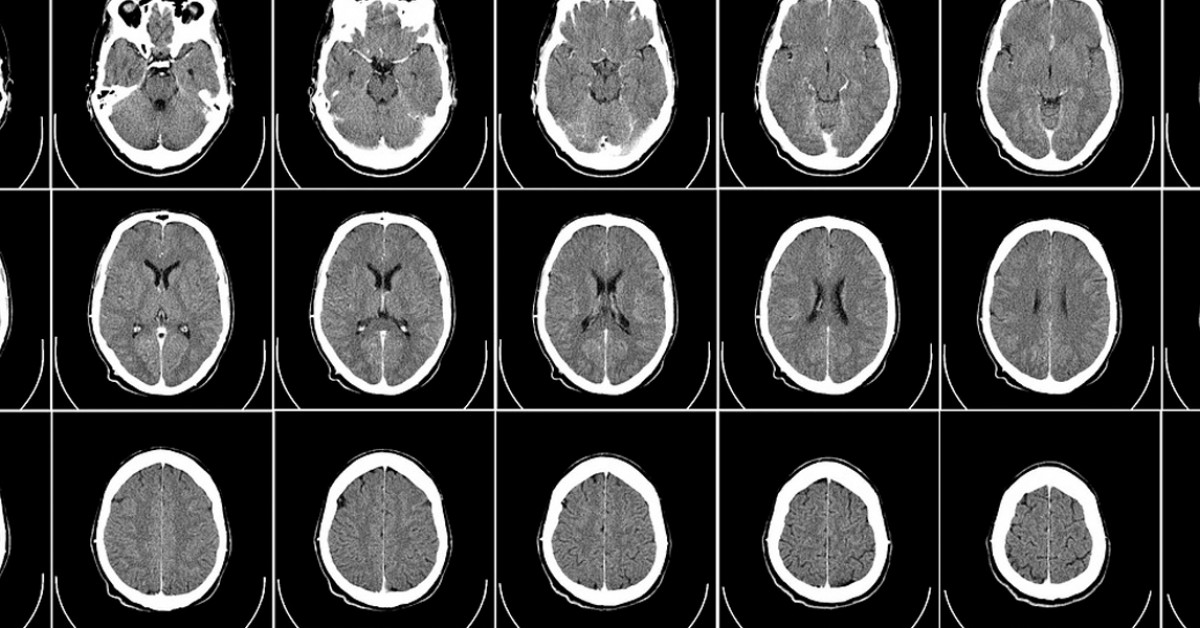

Een hersenschudding is een lichte vorm van hersenletsel. Het is meestal het gevolg van een flinke klap tegen je hoofd. Herkennen. Hoe kun je een hersenschudding herkennen? Iemand kan na een botsing of klap even buiten bewustzijn raken. Ook kan het zo zijn dat diegene niet meer weet wat er is gebeurd.. Een hersenschudding is letsel van de hersenen dat is veroorzaakt door een val of stoot op het hoofd. Bij een hersenschudding worden uw hersenen korte tijd letterlijk door elkaar geschud. Voor korte tijd kunt u het bewustzijn verliezen. Van het ongeval en van enige tijd daarvoor herinnert u zich soms niets meer.